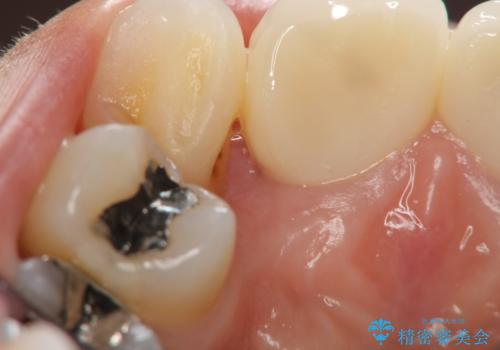

- 幼少時にぶつけ、神経を取った歯の審美改善を求めて来院されました。

X線写真より不十分な根管治療、根尖病変、前歯の変色が認められます。

歯根の近接のみられる右上側切歯を抜去し、根管治療を伴うセラミック治療を計画します。

- 26万円(仮歯・ファイバーコア・ジルコニアクラウン×2)費用は治療当時の料金となります